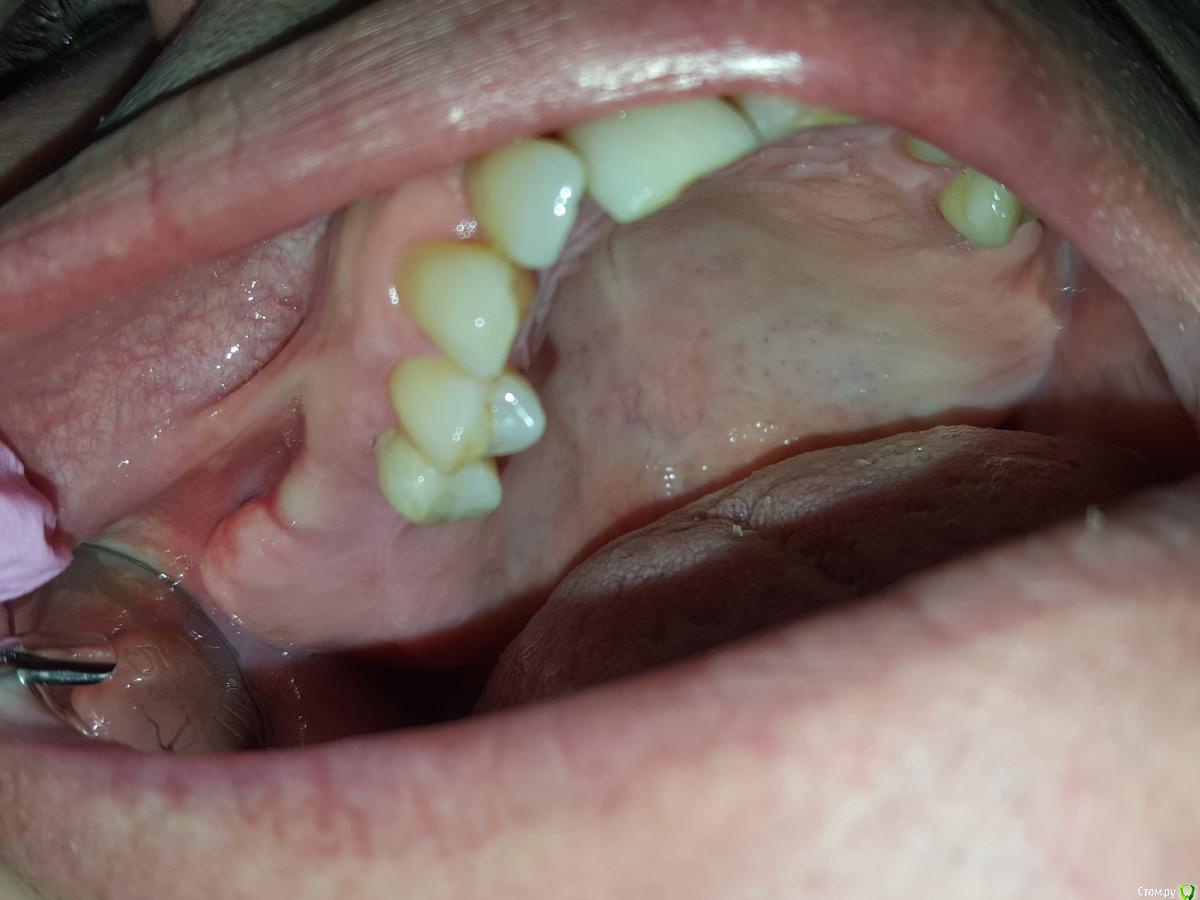

Gennadiy Опубликовано 5 февраля, 2016 Поделиться Опубликовано 5 февраля, 2016 Добрый день, подскажите кто что думает по этому поводу , пациент хочет импланты . Зубы удалены примерно лет назад. Ссылка на комментарий

red_butler Опубликовано 5 февраля, 2016 Поделиться Опубликовано 5 февраля, 2016 Экзостозы, лишней кости радоваться нужно, в пазуху отправите. 15 Ссылка на комментарий